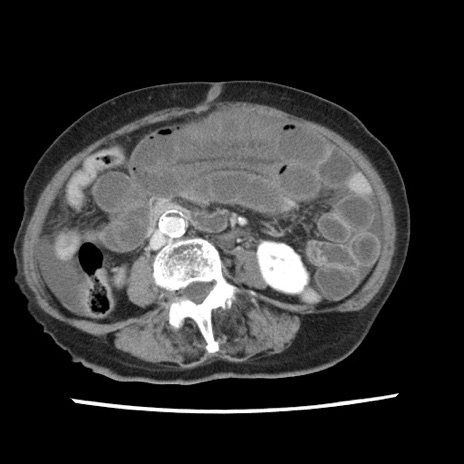

冠状断像

症例1(横断像)

【症例】80歳代女性

【主訴】腹痛

【現病歴】8時間前から腹痛あり来院。

【既往歴】糖尿病、脂質異常症、子宮体癌にて子宮全摘術

【身体所見】意識清明・会話良好だが腹痛で苦悶様、全腹部にわたって反跳痛と圧痛あり

【データ】WBC 13600、CRP 0.14、LDH 224、CK 90